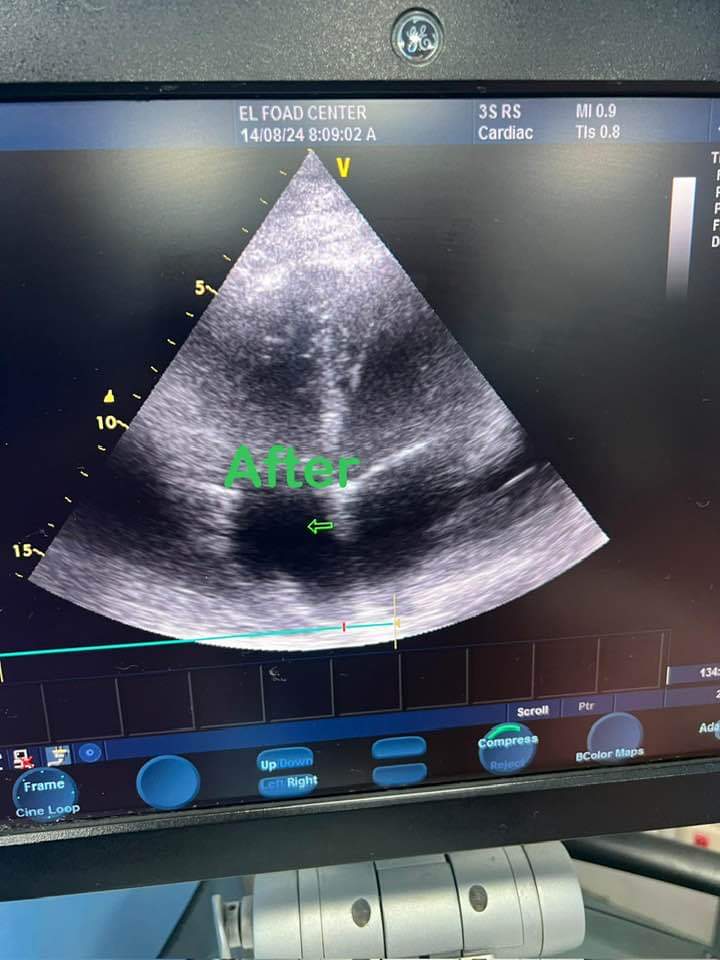

وتابع الدكتور حلمي عبد الرحمن: بمراجعة الحالة الإكلينيكية للمريضة وعمل الموجات الصوتية للقلب تبين عدم صحة التشخيص مع تجمع للسوائل حول عضلة القلب بكميات كبيرة جعلت القلب كأنه يسبح في بركة من السوائل الأمر الذي أدى إلى تأثر العلامات الحيوية وعدم قدرة القلب على القيام بمهامه.

وأوضح أنه تم تحضير المريضة للدخول للعمليات وفي وقت قياسي وبدون انتظار أي إجراءات تم دخولها العمليات وسحب ما يقرب من لتر من السائل حول عضلة القلب حتى عادت المريضة وعلاماتها الحيوية لمعدلاتها الطبيعية.